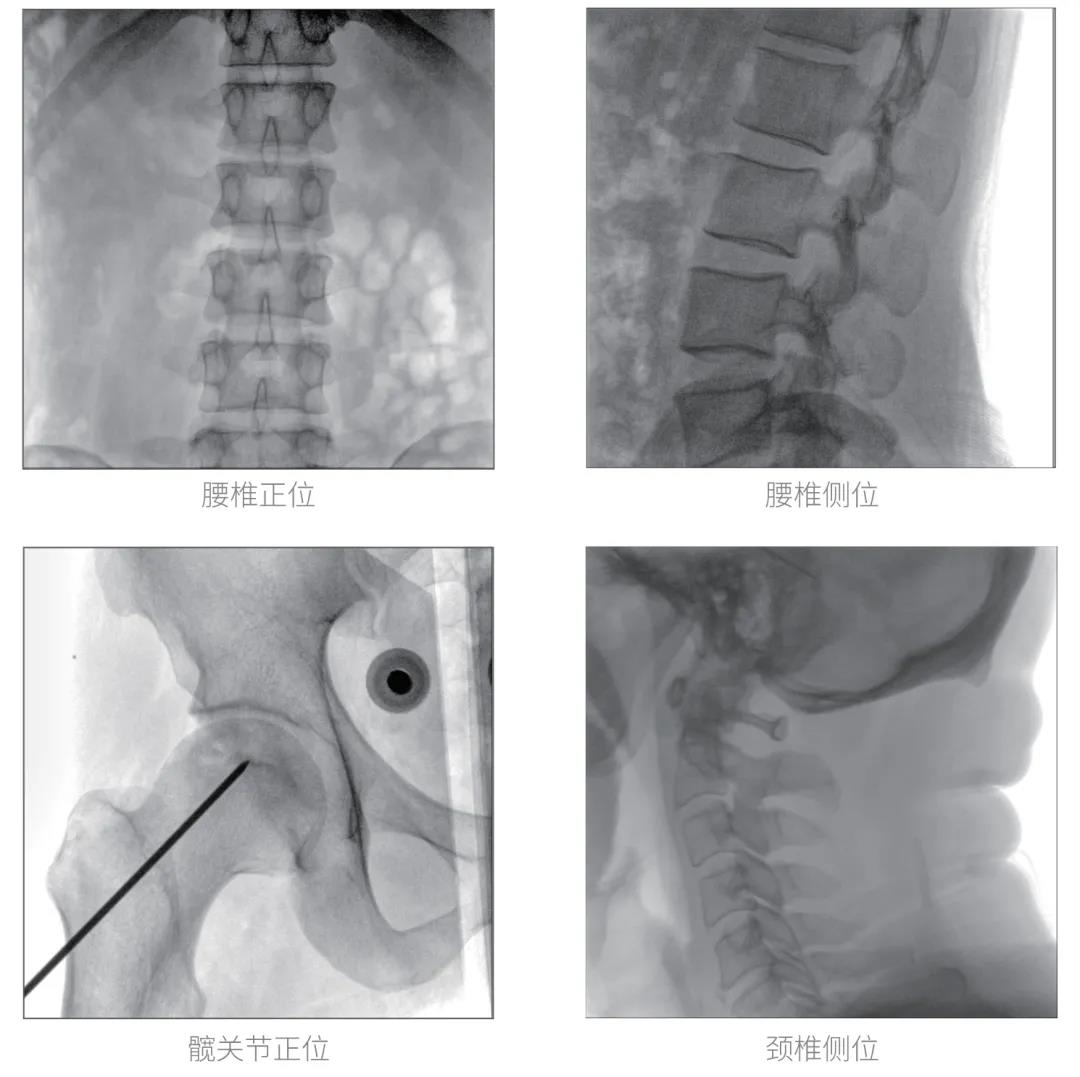

經(jīng)過(guò)認(rèn)真詳盡的設(shè)備審核驗(yàn)收,“慧瞳”正式投入使用,普愛(ài)醫(yī)療一體化平板C形臂采取的動(dòng)態(tài)平板探測(cè)器和智能圖像處理技術(shù),讓臨床圖像更加清晰。

普愛(ài)醫(yī)療一體化平板C形臂“慧瞳”采用小巧緊湊的一體化機(jī)架設(shè)計(jì),配合高性能的動(dòng)態(tài)平板探測(cè)器,移動(dòng)靈活,成像清晰,是各級(jí)醫(yī)院開(kāi)展骨科及其相關(guān)外科手術(shù)的科室使用的理想設(shè)備。

智能化實(shí)時(shí)圖像處理技術(shù),自動(dòng)分析圖像并進(jìn)行增強(qiáng)處理,減少臨床應(yīng)用中處理圖像時(shí)的繁瑣操作,快速提供優(yōu)質(zhì)圖像方便完成臨床工作。